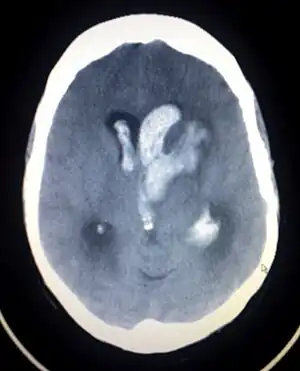

| An intracranial hemorrhage, one cause of altered level of consciousness | |

A lowered level of consciousness indicate a deficit in brain function.[4] Level of consciousness can be lowered when the brain receives insufficient oxygen (as occurs in hypoxia); insufficient blood (as occurs in shock, in children for example due to intussusception); or has an alteration in the brain's chemistry.[3] Conditions of the heart and conditions of the lungs can alter consciousness. Metabolic disorders such as diabetes mellitus and uremia can alter consciousness.[12] Hypo- or hypernatremia (decreased and elevated levels of sodium, respectively) as well as dehydration can also produce an altered LOC.[13] A pH outside of the range the brain can tolerate will also alter LOC.[9] Exposure to drugs (e.g. alcohol) or toxins may also lower LOC,[3] as may a core temperature that is too high or too low (hyperthermia or hypothermia). Increases in intracranial pressure (the pressure within the skull) can also cause altered LOC. It can result from traumatic brain injury such as concussion.[12] Ischemic stroke and brain bleeding are other causes of altered consciousness.[12] Infections of the central nervous system may also be associated with decreased LOC; for example, an altered LOC is the most common symptom of encephalitis.[14] Neoplasms within the intracranial cavity can also affect consciousness,[12] as can epilepsy and post-seizure states.[9] A decreased LOC can also result from a combination of factors.[12] A concussion, which is a mild traumatic brain injury (MTBI) may result in decreased LOC.